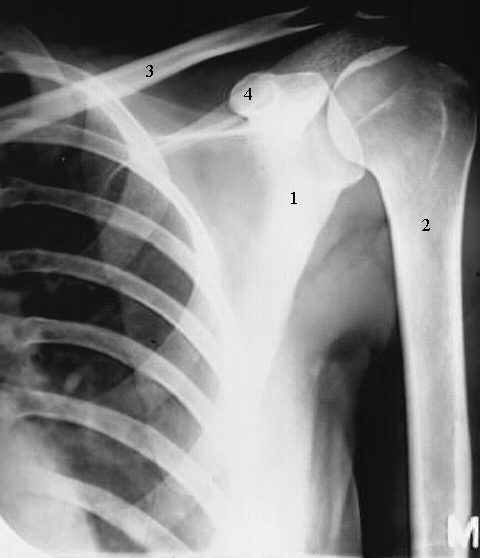

Radiology Images

Upper Limbs:Shoulder Bones:

1. Scapula

2. Humerus

3. Clavicle

4. Coracoid Process.